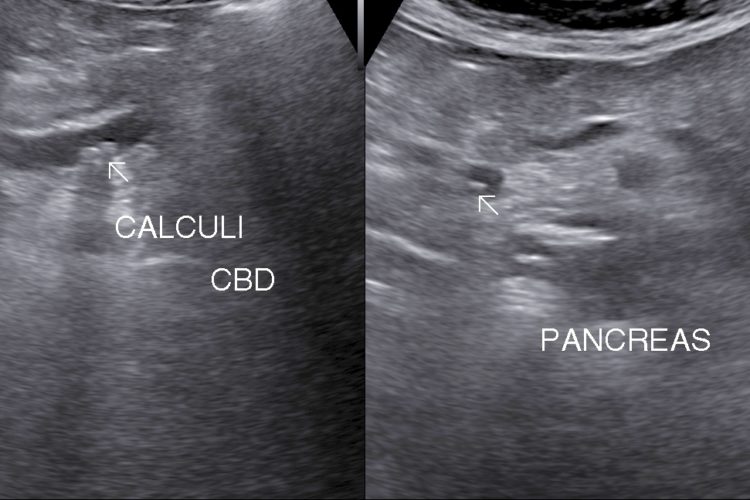

• Choleydocholithiasis (Calculus/ Calculi in Biliary tree): Passage of calculus/caculli in common bile duct leads to biliary colic, nousea, vomitting.

• Surgical jaundice and pancreatitis are complication.